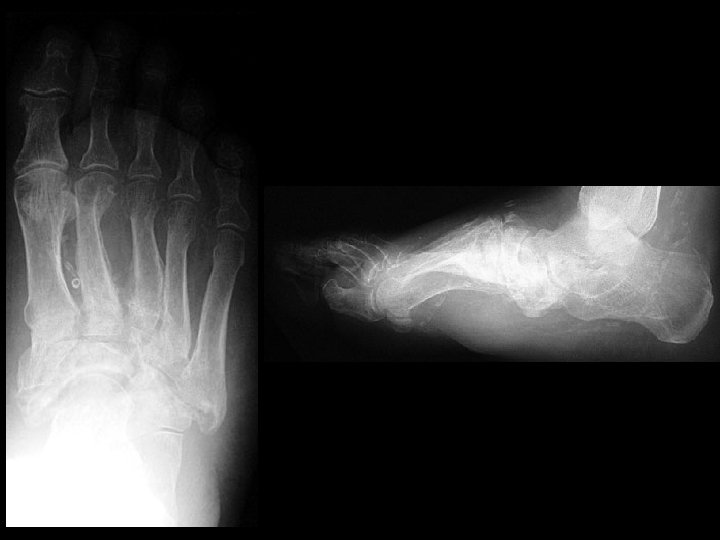

Diabetic Charcot foot & Lisfranc fracture dislocations • Findings: – Destruction, debris, dislocation, and increased density of Lisfranc joints – Pes planus – Vascular calcifications indicative of DM • ddx: – osteomyelitis

Gout • Findings: – Large erosions with overhanging margins at the great toe MTP joint – Dense periarticular swelling – Sparing of the joint space • ddx: – NONE! – This is an Aunt Minnie!